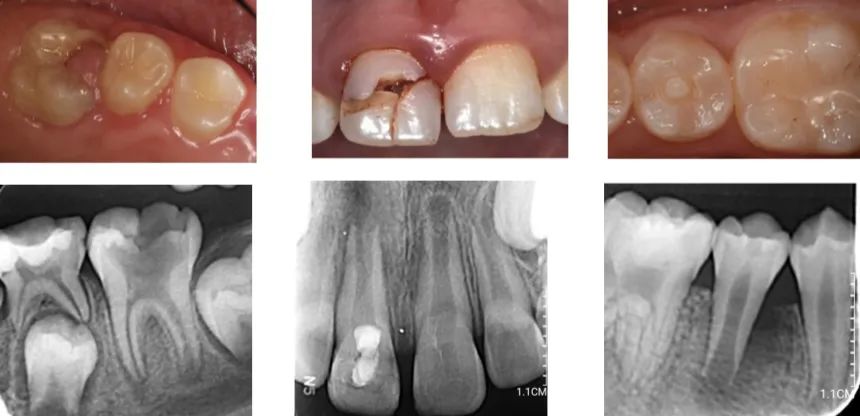

经过牙体牙髓学科郜慧慧医师检查发现,媛媛的右上门牙为牙根未发育成熟的年轻恒牙,且牙髓完全坏死,可以通过牙髓血运重建术治疗,来实现右上门牙的“牙髓再生”及牙根的继续发育。

年轻恒牙指恒牙萌出后3-5年的时间内形态和结构尚未发育完全的牙齿,表现为牙根短小,根管壁薄弱,根尖孔敞开的特性。此时的牙齿一旦因为外伤、龋坏或是牙发育畸形导致牙髓坏死或慢性根尖周炎,患牙的牙根就此停止发育,最终导致患牙的脱落,严重的可影响患儿的颌面部发育(颜值)。

对于适合做牙髓再生治疗的病例,在显微镜下去除感染坏死的牙髓组织,并通过大量冲洗液的冲洗和根管内封药达到理想的根管消毒效果。

图片来源于网络

第二次治疗一般是在1-2周后,患牙疼痛肿胀等症状消退,可以进入根尖引血的步骤,利用根管锉的机械刺激将根尖血液引入根管,等到血液充盈整个根管并静置形成血凝块,在上方使用生物陶瓷材料等进行严密的冠方封闭。

治疗结束后1、3、6、12月,需要密切随访,通过临床及影像学检查评估患牙治疗效果。